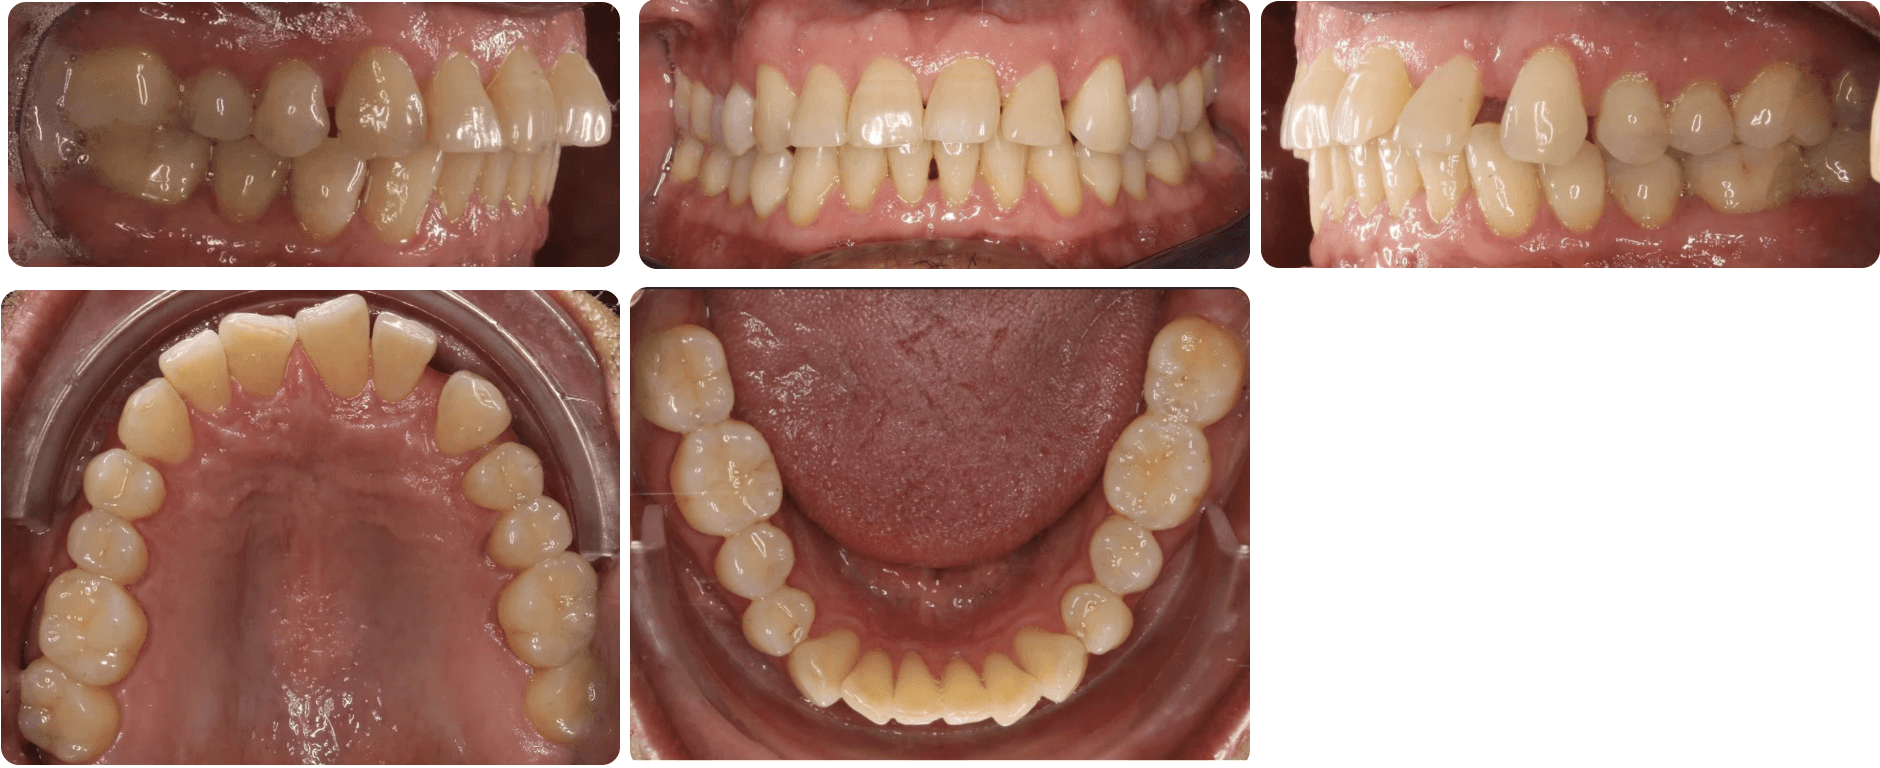

Diagnosis: A mix of crowding and mild spacing, moderate curve of Spee, black triangles, significant overjet, reverse smile display

Adjuncts: Bite ramps, attachments, IPR

Initial treatment

INTRAORAL